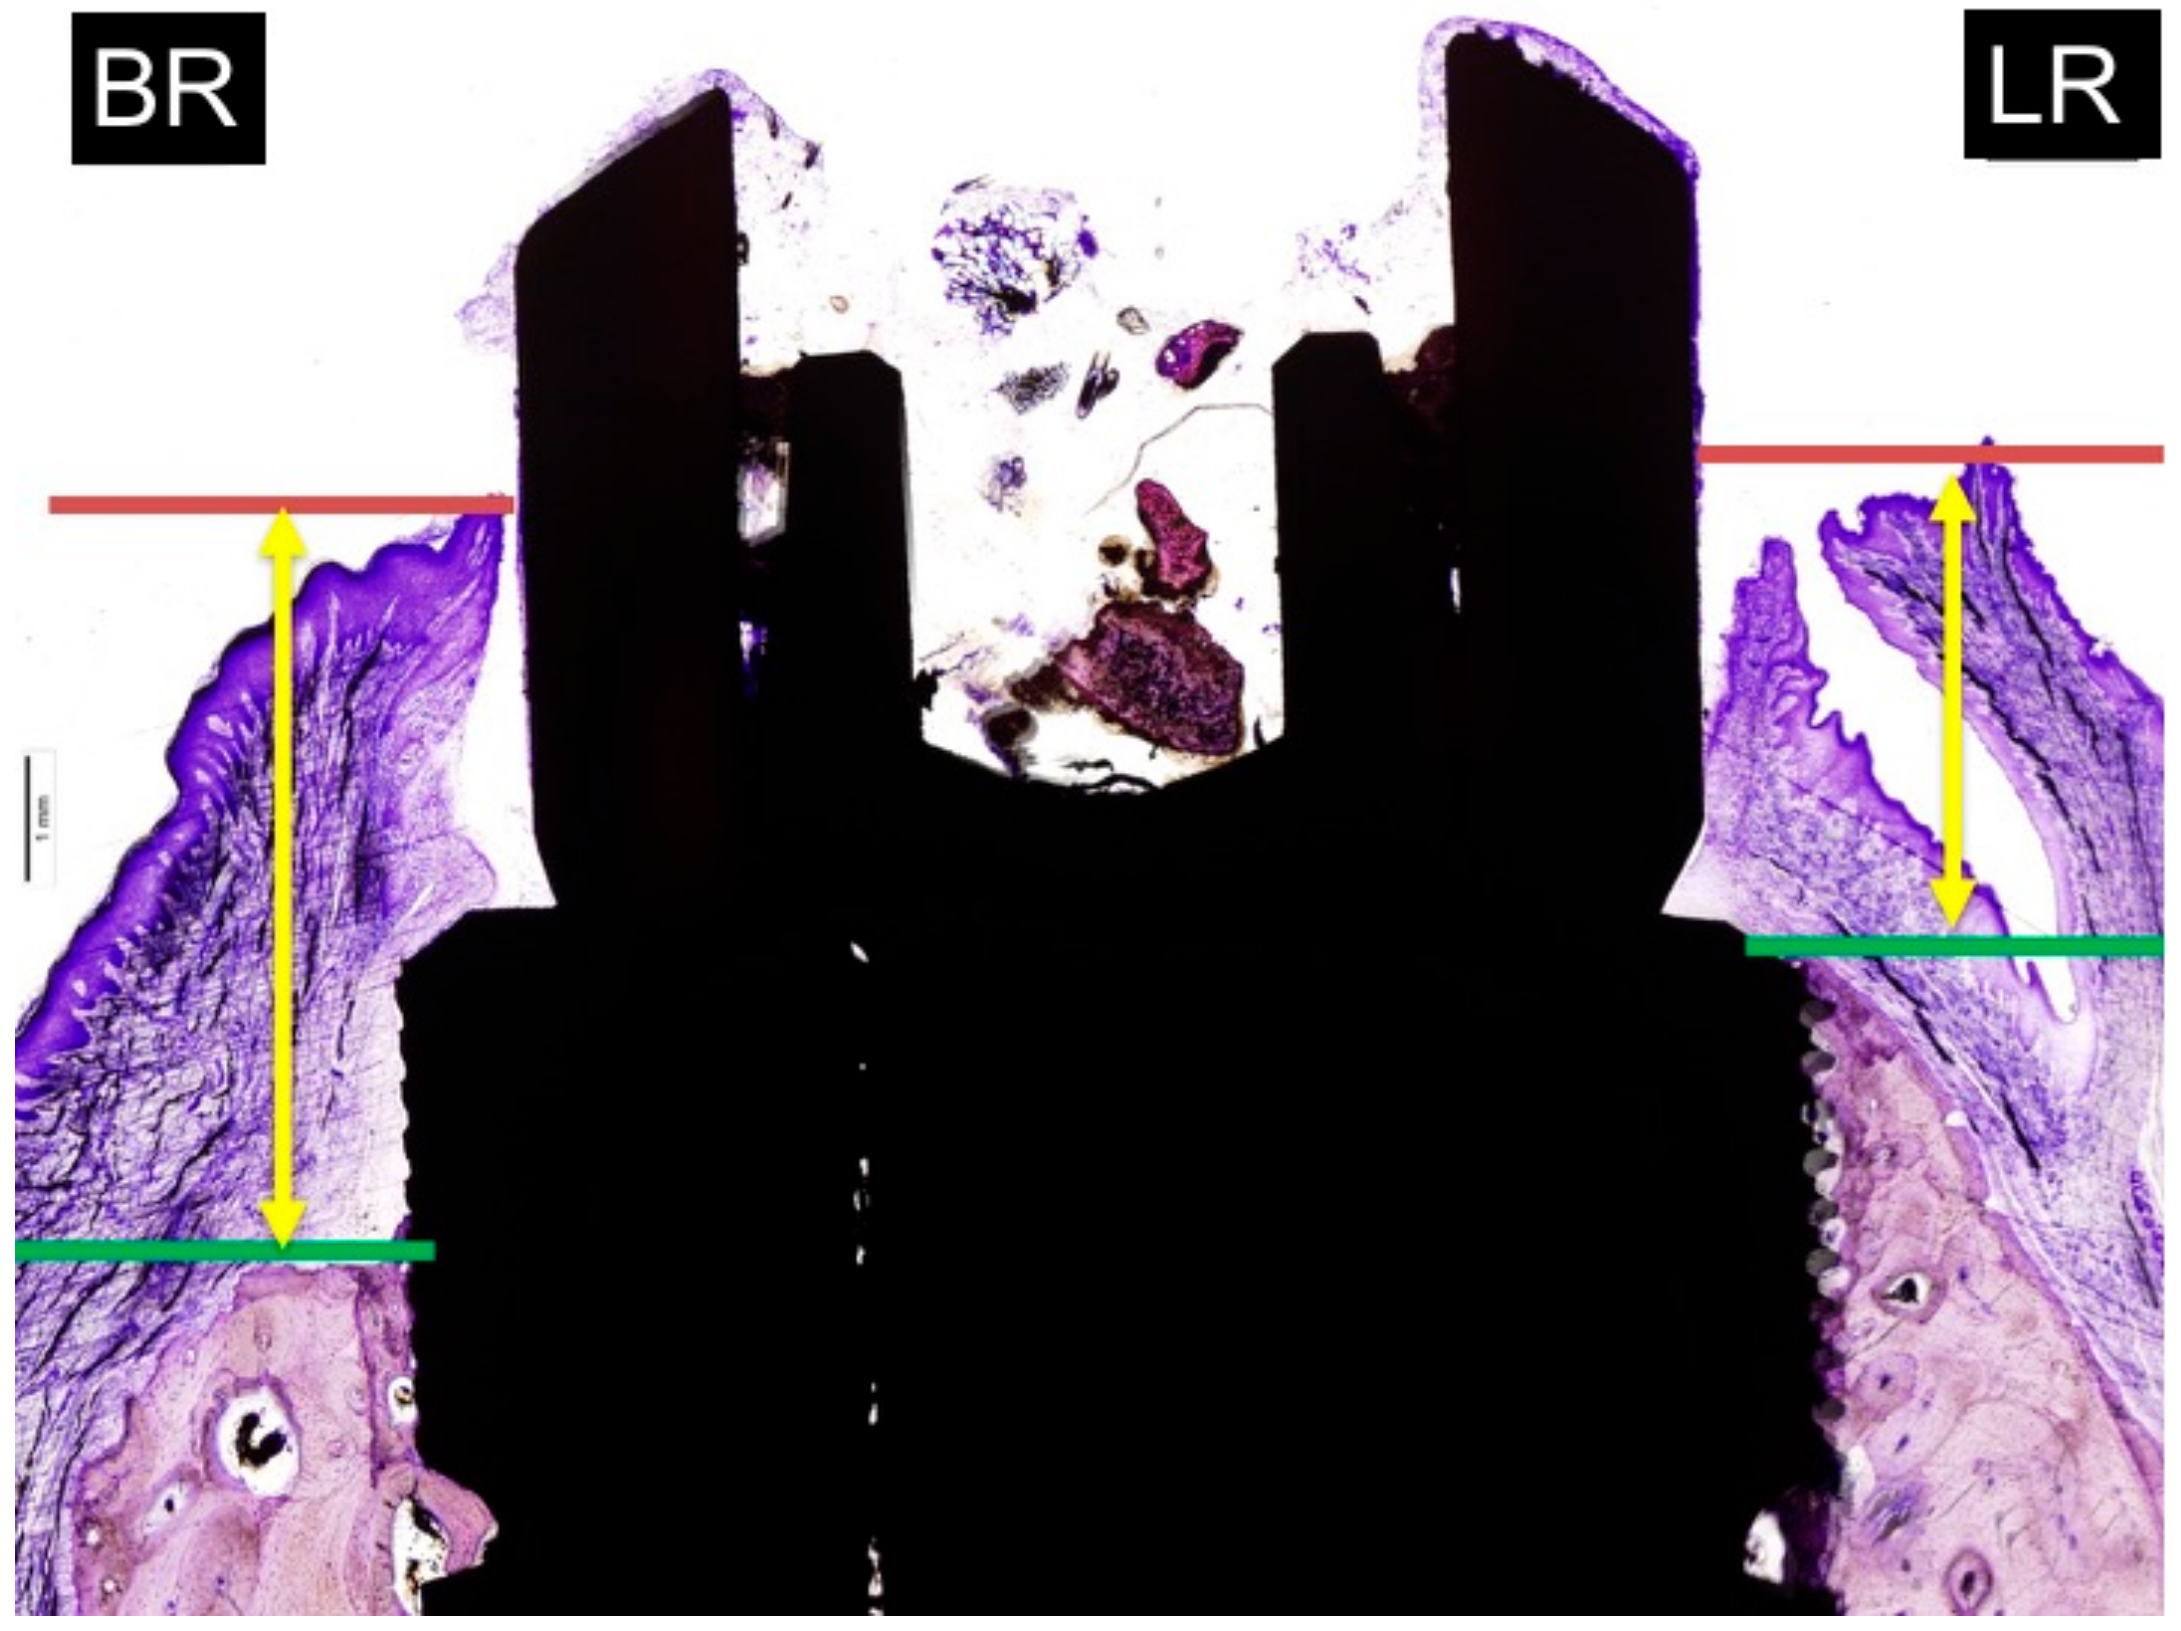

The soft tissue thickness was measured from the most higher point of the gingival mucosa to the most coronal point of the crestal bone. The measurements of buccal and lingual mean and SD were expressed in millimetres (Figure 6).

Figure 6.

Measurements of soft tissue thickness: BR: buccal crest resorption (distance from the top of the implant shoulder to the first BIC in the buccal crestal side. LR: lingual crest resorption (distance from the top of the implant shoulder to the first BIC in the lingual crestal side).